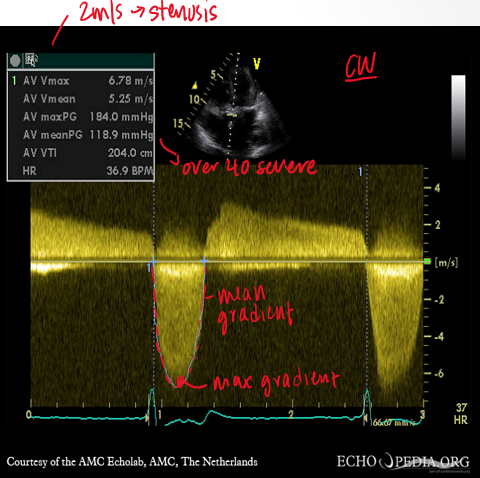

what are the main measurements to quantify severity of ao stenosis?

max ao jet velocity

mean transao pressure gradient

continuity equation valve area

what doppler is used to measure ao stenosis?

CW bc of high velocities (3-6m/s)

how is mean transo pressure gradient calculated?

by tracing the velocity curve and avering instantaneous gradients over systolic ejection period

grading for AS severity